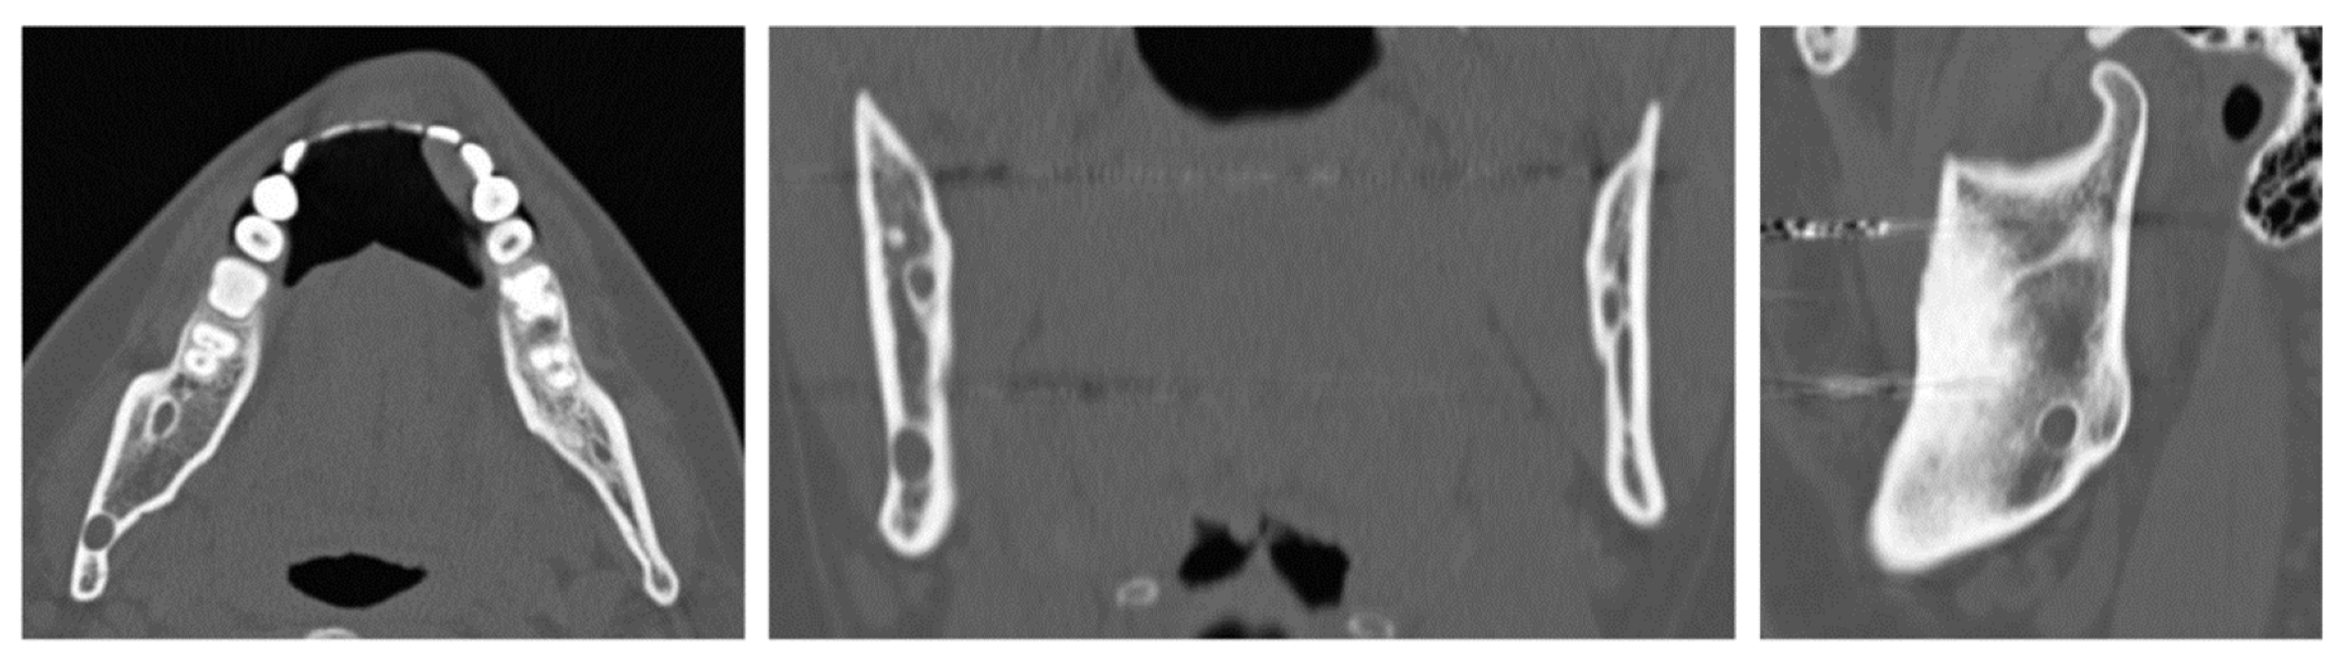

A 32-year-old patient came to our attention during an oncological follow-up, which included the execution of an OPT (Orthopantomography) X-ray, revealing a new osteolytic lesion at the right mandibular angle. In 1996, the patient underwent surgical removal of a unicystic ameloblastoma at another facility. We reviewed the patient’s most recent radiological documentation, which was an OPT X-ray taken 12 years earlier (8 years after the initial surgery) and showed no mandibular lesions. A mandibular CT scan was requested to better define the lesion (Figure 10).

Figure 10. Evidence on the mandibular CT scan of the appearance of a new osteolytic lesion, appreciable on axial, coronal, and sagittal views.